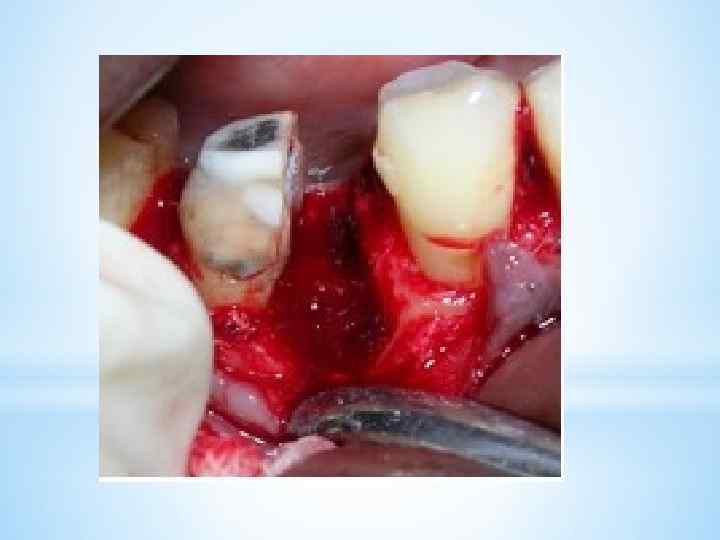

При гемисекции зуба под местной анестезией проводится вертикальное рассечение многокорневого зуба с последующим удалением той части, в области верхушки корня которой имеется хронический очаг инфекции. Перед операцией гемисекции хирург пломбирует каналы корней зубов, подлежащие сохранению. Иногда при гемисекции врачу приходится отслаивать слизистонадкостничный лоскут, после чего с помощью бормашины удаляется поврежденный корень. Зуб после гемисекции полностью сохраняет свою функциональность и может быть использован для установления ортопедических конструкций.

При гемисекции зуба под местной анестезией проводится вертикальное рассечение многокорневого зуба с последующим удалением той части, в области верхушки корня которой имеется хронический очаг инфекции. Перед операцией гемисекции хирург пломбирует каналы корней зубов, подлежащие сохранению. Иногда при гемисекции врачу приходится отслаивать слизистонадкостничный лоскут, после чего с помощью бормашины удаляется поврежденный корень. Зуб после гемисекции полностью сохраняет свою функциональность и может быть использован для установления ортопедических конструкций.

*Возможно два варианта проведения операции гемисекции. *В первом случае принцип хода операции следующий. Производится сепарация коронки, то есть коронку распиливают до области бифуркации (места разделения на корни), после чего происходит удаление корня. *Другой вариант – лоскутный метод. Хирург отслаивает слизисто-надкостничный лоскут, после чего вырезает причинный корень. Освободившуюся полость заполняют веществом, способствующим заживлению тканей. Лоскут возвращается на место и ушивается. *

*Возможно два варианта проведения операции гемисекции. *В первом случае принцип хода операции следующий. Производится сепарация коронки, то есть коронку распиливают до области бифуркации (места разделения на корни), после чего происходит удаление корня. *Другой вариант – лоскутный метод. Хирург отслаивает слизисто-надкостничный лоскут, после чего вырезает причинный корень. Освободившуюся полость заполняют веществом, способствующим заживлению тканей. Лоскут возвращается на место и ушивается. *

*-Алгоритм проведения: выбор анестетика; - выбор нужных инструментов; - подготовка бормашины и наконечника к операции; - обработка рук; - проведение анестезии; - разрез слизистой, надкостницы в проекции корней зуба; - отслоение слизисто-надкостничного лоскута, оголение кости альвеолярного отростка; - снятие бором кости над корнем, который удаляется; - проведение бором, диском сепарации коронки зуба; - удаление пораженной части зуба (половина коронки и корень); - нивелирование острых костных краев; - удаление кюретожной ложкой грануляций; - обработка раны 3% р-ром Н 202, высушивание; - укладывание лоскута на место; - накладывание швов.

*-Алгоритм проведения: выбор анестетика; - выбор нужных инструментов; - подготовка бормашины и наконечника к операции; - обработка рук; - проведение анестезии; - разрез слизистой, надкостницы в проекции корней зуба; - отслоение слизисто-надкостничного лоскута, оголение кости альвеолярного отростка; - снятие бором кости над корнем, который удаляется; - проведение бором, диском сепарации коронки зуба; - удаление пораженной части зуба (половина коронки и корень); - нивелирование острых костных краев; - удаление кюретожной ложкой грануляций; - обработка раны 3% р-ром Н 202, высушивание; - укладывание лоскута на место; - накладывание швов.